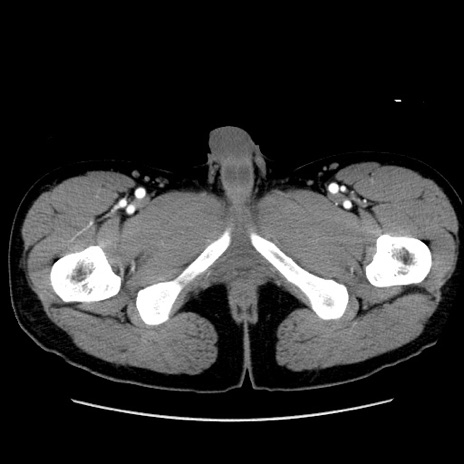

症例36(横断像)

【症例】20歳代 男性

【主訴】心窩部痛

【現病歴】今朝より上腹部痛あり。一旦軽快していたが再度出現したため救急要請。昨日夕に白身の魚を含む刺身を食べた。

【身体所見】BP 136/89mmHg、HR 74/min、BT 37.0℃、腹部:膨満、軟、心窩部に圧痛あり。反跳痛なし、筋性防御なし、腸雑音やや亢進あり。

【データ】WBC 17700、CRP 0.48